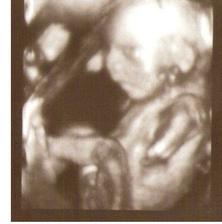

6.11. jsme podstoupili II. screening a bylo potvrzeno, že čekáme chlapečky 🙂

7.11. jsme byly na 3D UTZ, kluci sebou mleli o stošest a jeden bude nejspíš celý tatínek 😀, neb když došlo na focení, tak si dal ruku před obličej a že se prý neukáže 🙂)))